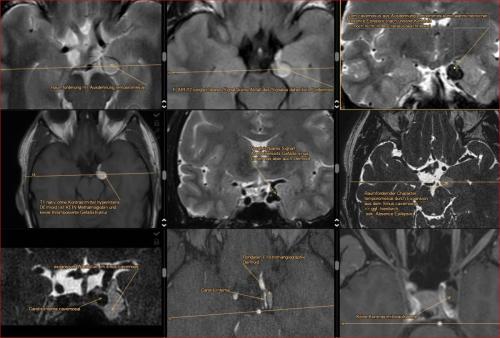

Aneurysma re. 7 mm Darstellung in einer DSA (digitalen Subtraktionsangiographie) links nur ein 2 mm „Baby-Aneurysma“ Im MRT war zuvor das linke Aneurysma aufgefallen, die Auflösung einer DSA ist technisch im MRT nicht erzielbar, beide A. liegen in der ACM Bifurkation jeweils, das re. Aneurysma wurde erfolgreich operiert, das linke Aneurysma wird kontrolliert.